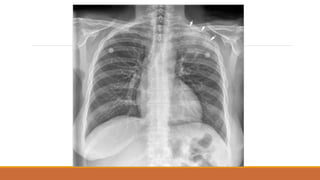

TRÀN KHÍ MÀNG PHỔI

• PHIM ĐỨNG:

• VÙNG SÁNG VÔ MẠCH NẰM NGOÀI LÁ TẠNG

• ĐƯỜNG MỜ CỦA LÁ TẠNG BAO BỌC NHU MÔ PHỔI XẸP

• TKMP ÁP LỰC: ĐẨY TRUNG THẤT VỀ ĐỐI BÊN, XẸP PHỔI THỤ ĐỘNG,VÒM

HOÀNH DẸT, RỘNG KHOẢNG LIÊN SƯỜN

• PHIM NẰM:

• GIỐNG PHIM ĐỨNG

• DH KHE SÂU

TKMP CHỤP TƯ THẾĐỨNG

TKMP CHỤP TƯ THẾNẰM: DH khe sâu